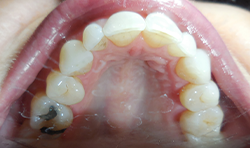

A patient presented to the practice complaining that her husband and daughter have told her she snores, at times wakes up gasping for air, short of breath and appears to be choking. The patient also stated she hasn’t slept well for the last 20 years.

Our clinical findings included a body mass index of 27, a constricted maxillary arch, retrognathic mandible, high palatal vault, tooth occlusal wear, Class IV Mallampati restricted airway and a familial history of sleep apnea (Figs. 1–3).

When the patient was younger, she had four premolar extractions during orthodontic intervention. These had now slightly relapsed, causing anterior crowding and reclining of her premolar and molars. In addition to the snoring, the patient was diagnosed with Hashimoto’s disease, which has also been correlated with obstructive sleep apnea.6 She also had a previous diagnosis of periodic limb movements of sleep (PLMS), for which she was on a higher-than-normal dosage of clonazepam. Clonazepam has also been linked to causing sleep apnea.7,8